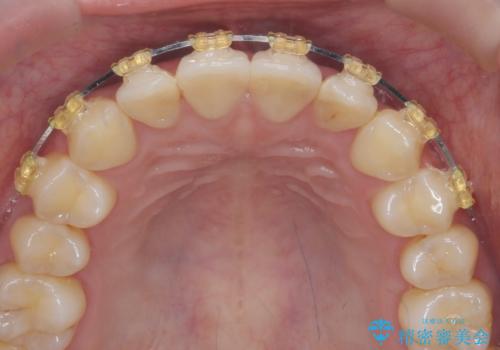

ワイヤー部分矯正治療を併用したマウスピース矯正治療

- 前歯のねじれ、深い噛み合わせ(ディープバイト)の改善を求めて来院されました。

マウスピースでは改善の難しい、歯のねじれ・ディープバイトを部分ワイヤー矯正で改善したのち、マウスピース矯正で全体の歯並びを整えていきます。

部分ワイヤー矯正を行ったことで前歯をしっかりと綺麗な歯並びへと導くことができました。